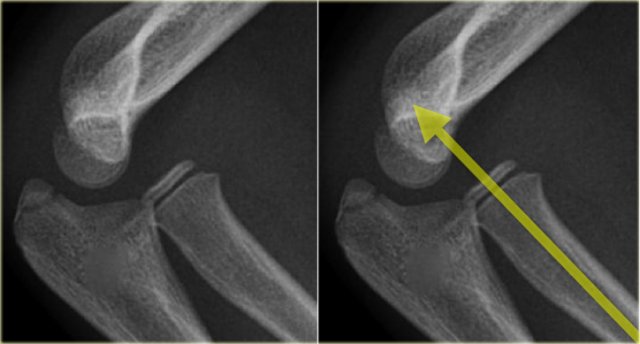

Radiocapitellar line

A line drawn through the centre of the radial neck should pass throught the centre of the capitellum, whatever the positioning of the patient, since the radius articulates with the capitellum (figure).

In dislocation of the radius this line will not pass through the centre of the capitellum.

On the left more examples of the radiocapitellar line.

The right lower image shows an obvious dislocation of the radius.

The radiocapitellar line ends above the capitellum.

This means that the radius is dislocated.

Did you also notice the olecranon fracture?

Whenever the radius is fractured or dislocated, always study the ulna carefully.